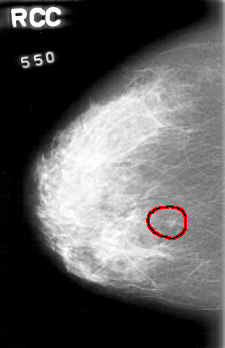

D_4022_1.RIGHT_CC

RIGHT_CC LINES 5206 PIXELS_PER_LINE 3361 BITS_PER_PIXEL 12 RESOLUTION 43.5 OVERLAY

FILE: D_4022_1.RIGHT_CC.OVERLAY

TOTAL_ABNORMALITIES 1

ABNORMALITY 1

LESION_TYPE MASS SHAPE ROUND MARGINS OBSCURED

ASSESSMENT 0

SUBTLETY 5

PATHOLOGY BENIGN

TOTAL_OUTLINES 1